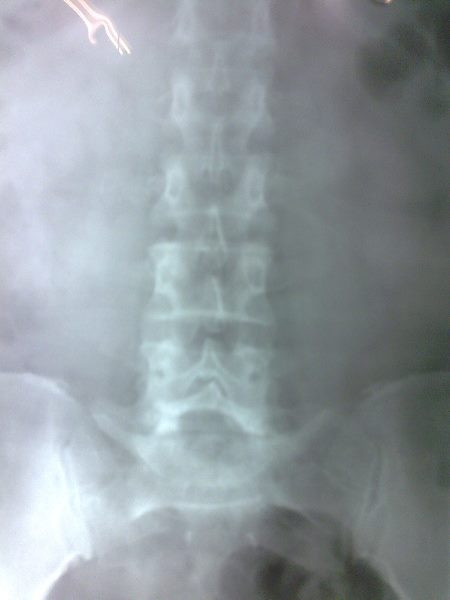

Radiografías con enfoque en fisiatría

Envíado por Dr. Hernán Darío Sánchez Ramos